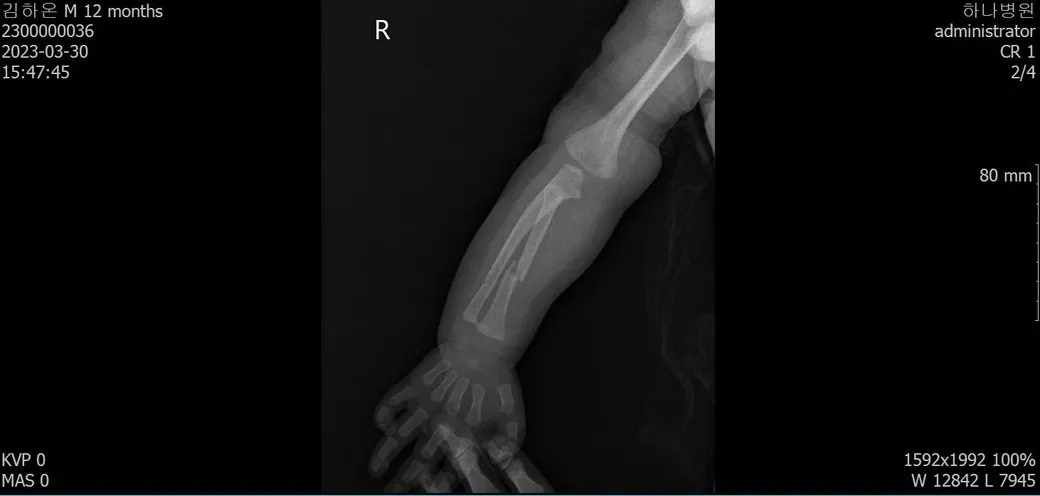

다름이 아니라, 첨부드린 엑스레이(X-ray) 사진처럼 골절 사실을 알게 되고 골절 발생 시점 대략적으로나마 추정시기를 파악하려고 문의 드리게 되었습니다

1) 3월 30일 촬영한 X-ray만으로 정확한 골절 시기를 100% 특정하는 데에는 한계가 있다는 점 충분히 인지하고 있기에 촬영날짜 기준으로 대략적으로 어느정도 시점에서 발생되었을 것으로 추측(ex 당일, 7~10일전, 7~14일 전, 10일 ~ 20일전, 14일 ~ 30일전 등등등)되는지 이해하고 싶습니다.

• 4번 째 사진

보호자분이 원하시는 것은 2023-03-30에 골절이 된 사진만 가지고 언제 골절이 되었는지 추정을 하고 싶다는 말씀이죠? 3번째 사진에서 주변살들이 많이 부어있거나 하지 않아서 시간이 어느 정도 지난 것으로 보이네요. 초기유합은 1-2개월 정도 걸리는 것으로 알려져 있는 것으로 알려져 있으니 그 정도를 생각할 수 있을 것 같네요. 추정일 뿐입니다.